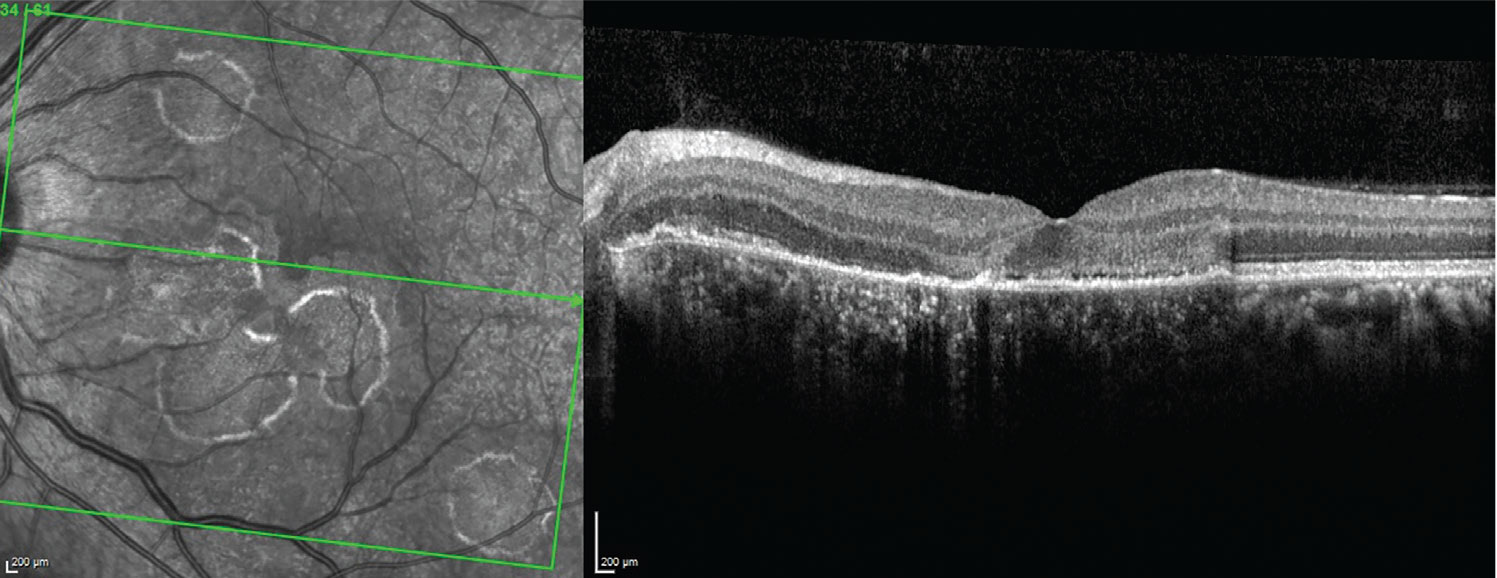

Fundus autofluorescence showed multifocal hypoautofluorescent lesions with surrounding hyperautofluorescence (Figure 1B). Optical coherence tomography showed attenuation of the retinal pigment epithelium, patchy loss of the ellipsoid zone and photoreceptors, and thickened and disorganized retinal laminations (Figure 2). Fluorescein angiography showed early blocking in the areas of the active choroidal lesions and late staining (Figure 3).

Figure 2. Optical coherence tomography of the left macula demonstrates ellipsoid zone loss, patchy photoreceptor layer loss, attenuation of the retinal pigment epithelium and thickened and disorganized retinal laminations. |